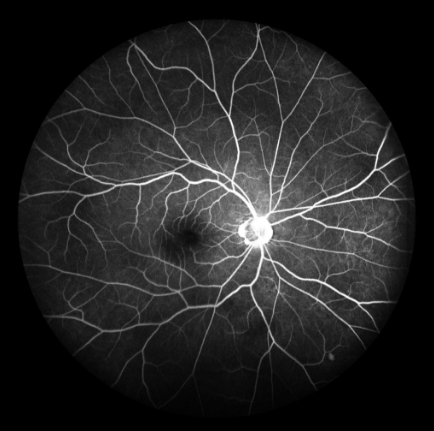

FFA是20世紀(jì)60年代發(fā)展的一項(xiàng)技術(shù)。1961年Navotny 和Alvis首次成功地用膠片記錄到熒光素流經(jīng)視網(wǎng)膜和脈絡(luò)膜血管的動(dòng)態(tài)過程,開創(chuàng)了眼底熒光血管造影的臨床應(yīng)用時(shí)代。如今,F(xiàn)FA主要用于觀察視網(wǎng)膜血管及其血液循環(huán)狀態(tài),高清晰攝像技術(shù)能動(dòng)態(tài)捕捉視網(wǎng)膜毛細(xì)血管的循環(huán)狀態(tài),間斷或連續(xù)采集可形成視網(wǎng)膜靜態(tài)的黑白圖像或動(dòng)態(tài)圖像,在診斷中敏感性強(qiáng),確診率高,能發(fā)現(xiàn)檢眼鏡或眼底照相下不易發(fā)現(xiàn)的視網(wǎng)膜深層微血管瘤,是判斷視網(wǎng)膜病變的“金標(biāo)準(zhǔn)”。

FFA影像